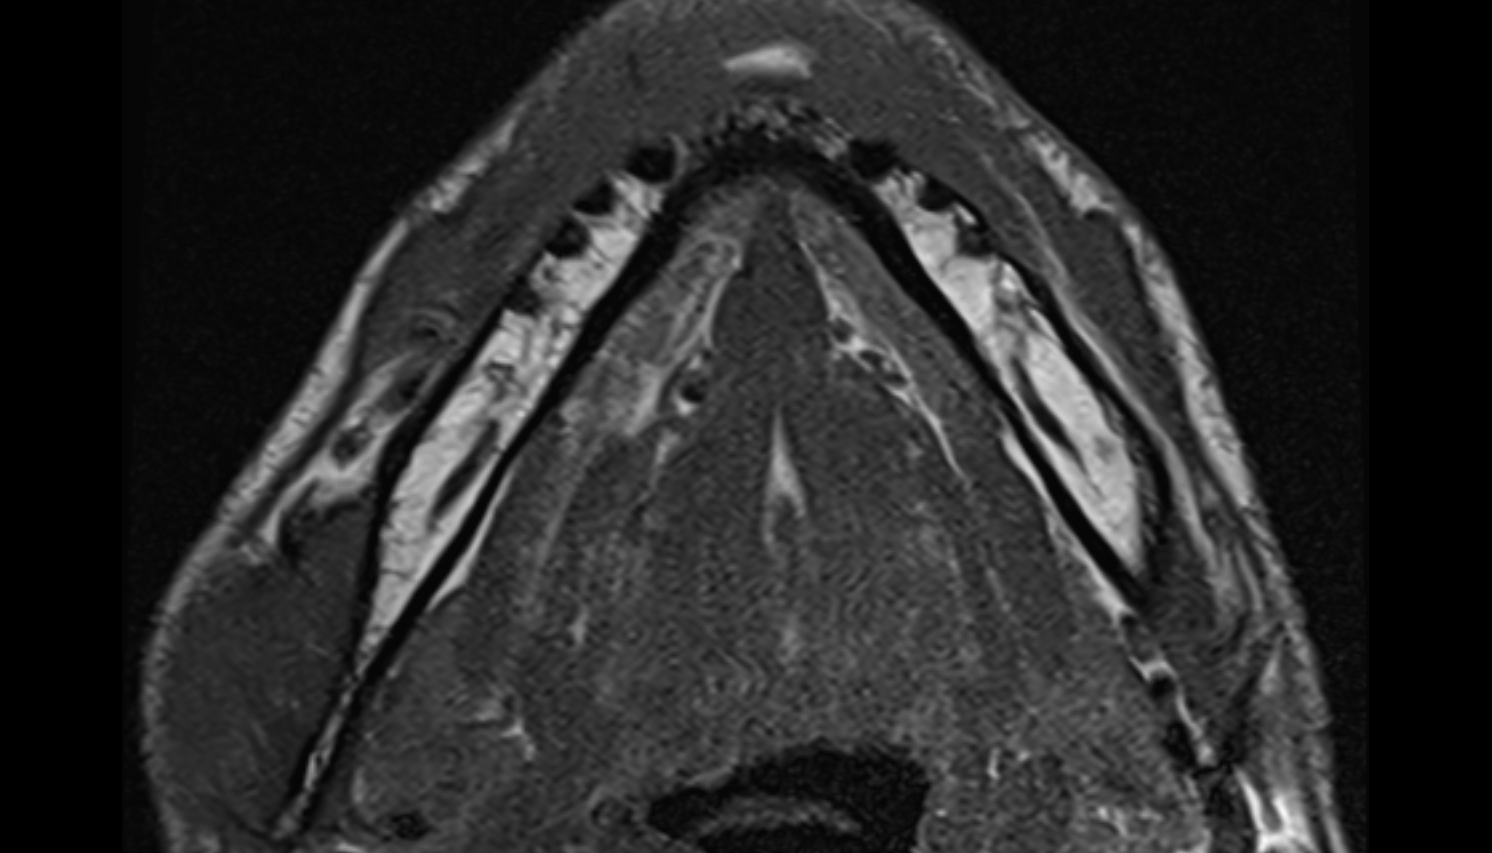

- Temporomandibular joint

- Mandibular condyle

- Mandibular fossa

- Deep part of masseter muscle

- Superficial part of masseter

- Superior head of lateral pterygoid muscle

- Inferior head of lateral pterygoid muscle

- Lateral pterygoid muscle

- Masseter muscle

- Medial pterygoid muscle

- Temporalis muscle